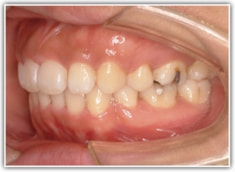

上顎前突ケース

治療法:表の矯正(T21ブラケット)

治療後(2年後)